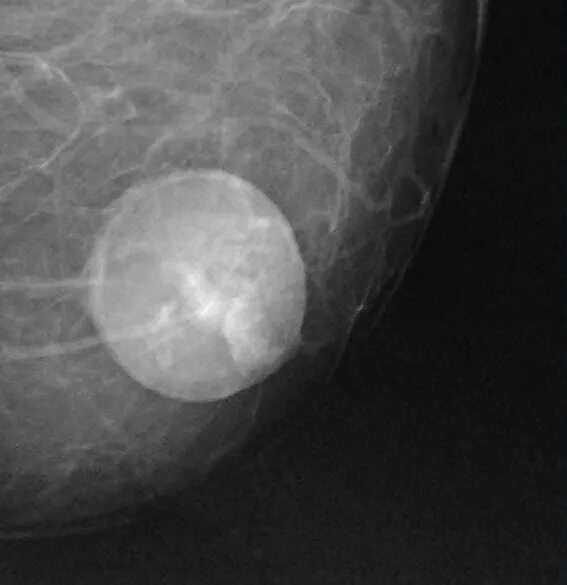

Как выглядит киста молочных желез